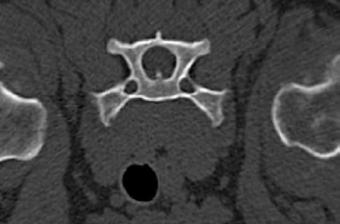

Se realiza radiografía de tórax (Fig. 1) que revela car-

diomegalia generalizada severa, índice de Buchanan de 15 cuerpos vertebrales, que puede corresponder a un severo aumento de las cámaras cardiacas, o a la presencia de líquido pericárdico. Se observa, además, un patrón pulmonar intersticial perihiliar, compatible con edema pulmonar, foco de neumonía o hemorragia pulmonar.

M. López,1 V. Fernández,2 J. Engel3 1Servicio de cardiología y diagnóstico por imagen. 2Servicio de cirugía. Laclinicaveterinaria. c/Marroquina 26. 28030 Madrid. 3Servicio de cardiología. ANICURA-Benipeixcar Hospital Veterinario. Avinguda de la Constitució 68, bajo izq. 46009 Valencia. ANICURA-San Francisco Hospital Veterinario. c/ Sant Francesc 65. 12500 Vinaròs (Castelló). ANICURA-San Vicente Hospital Veterinario. c/ Veterinario Manuel Isidro Rodríguez García 17. 03690 San Vicente del Raspeig (Alicante). Figura 1. Radiografía lateral de tórax en la que se observa cardiomegalia generalizada, VHS 15. Patrón alveolar intersticial compatible con edema pulmonar. Patrón vascular mixto y patrón bronquial en lóbulos caudales, compatible con bronquitis crónica, mineralización por degeneración senil.

En el caso que presentamos podemos confirmar cardiomegalia severa y edema pulmonar dado que el estudio radiológico del tórax permite establecer el tamaño cardiaco y valorar el patrón pulmonar. La insuficiencia cardíaca congestiva izquierda se caracteriza por un patrón intersticial, que puede evolucionar a patrón alveolar en la región perihiliar que tiende a distribuirse hacia caudodorsal, característico del edema pulmonar cardiogénico, patrón vascular venoso.